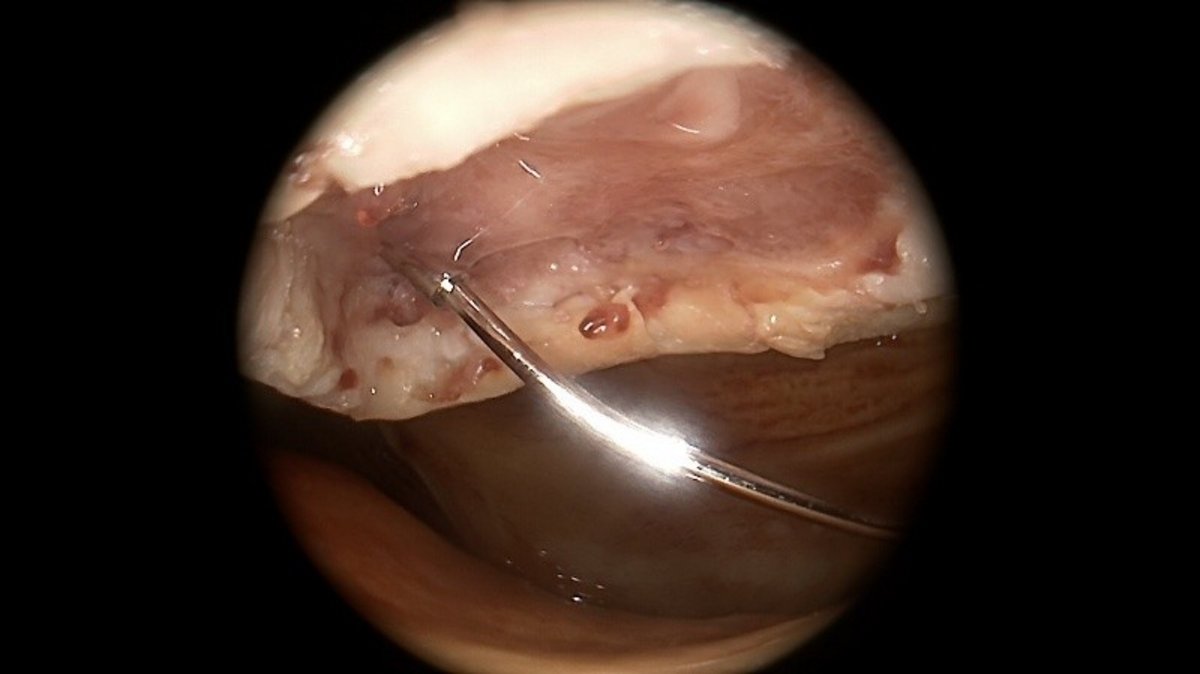

Bei jungen Patienten mit Meniskusverlust besteht auch die Möglichkeit einer sog. Meniskustransplantation, um langfristig das Fortschreiten der Arthrose hinauszuzögern. Hierbei wird aus einer Spenderbank ein bzgl. Größe und Form passender Spendermeniskus ausgewählt und nach Entfernung des defekten Eigenmeniskus im Gelenk fixiert.